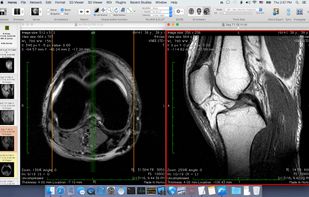

Free open source DICOM viewer for macOS, designed for 64-bit systems and based on OsiriX, offers advanced visualization, multimodal image fusion, measurement tools, image processing, PACS integration, file export, privacy features, and plugin support.

OsiriX is an image processing software dedicated to DICOM images (".dcm" / ".DCM" extension) produced by imaging equipment (MRI, CT, PET, PET-CT, SPECT-CT, Ultrasounds, ...). It is fully compliant with the DICOM standard for image comunication and image file...